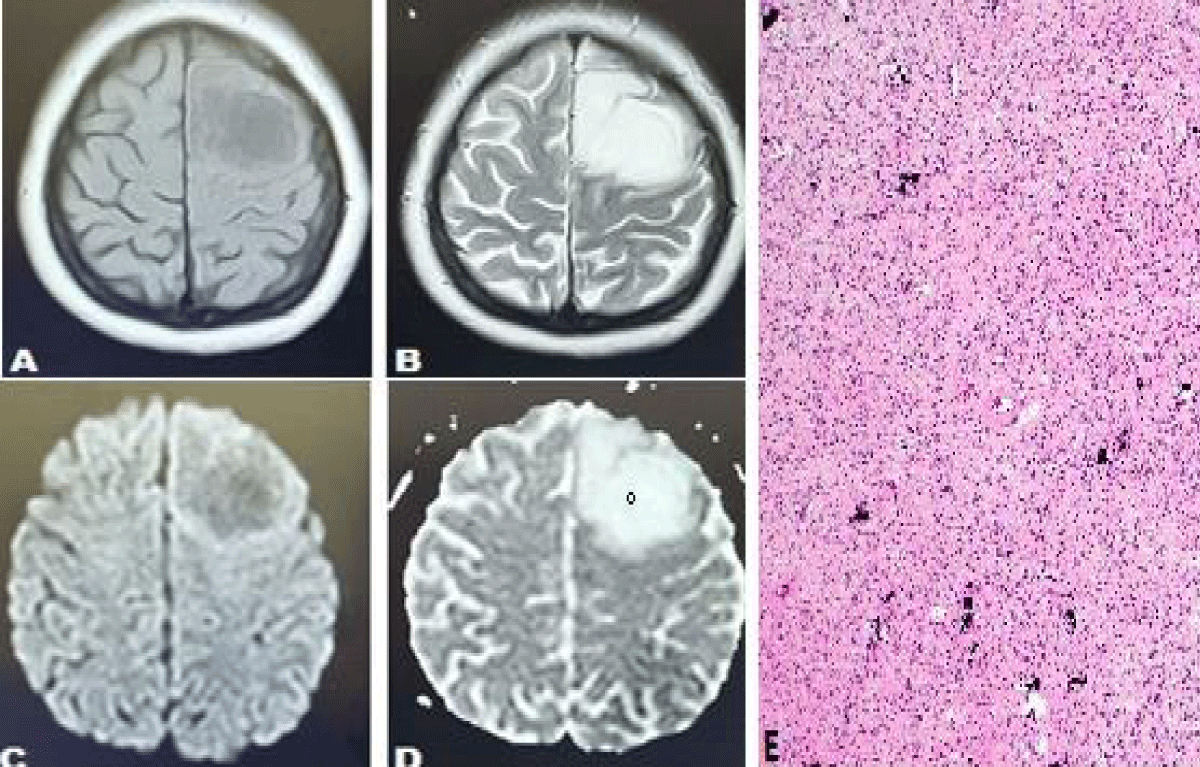

Figure 4: Case of 44 years female presented with headache and an episode of seizures. Axial T1 weighted sequences (T1WS) (A) and T2 weighted sequences (T2WS) (B) show an abnormal signal intensity lesion in the left frontal lobe appearing hypointense on T1WS and hyperintense on T2W sequences and demonstrating facilitated diffusion on Diffusion-weighted images (DWI) (C) and ADC map (D) with a high ADC value of 1123 x 10-6 mm2 /sec. (demonstrating low-grade glioma). (E) Histopathology report showed scattered microcalcifications which are characteristic of oligodendroglioma.

Figure 3: Case of 56 years old ale presenting with headache and left-sided body weakness (high-grade glioma). Axial T2 weighted sequences (T2WS) (A) axial T1 weighted sequences (T1WS) (B) axial and sagittal post-contrast T1WS (C, D) shows an abnormal signal intensity lesion in the high front temporal lobe extending into genu of the corpus callosum and basal ganglia appearing hypointense on T1WS and hyperintense on T2W sequences with mass effect and edema, demonstrating enhancement on post contrast images (C, D) along with a restriction on Diffusion-weighted images (DWI) (E) and ADC map (F) with a low ADC value of 137 x 10-6 mm2 /sec. (Favoring high-grade glioma). (G) Histopathology showed necrosis and sheets of irregular or elongated cells with pleomorphic nuclei consistent with glioblastoma area.